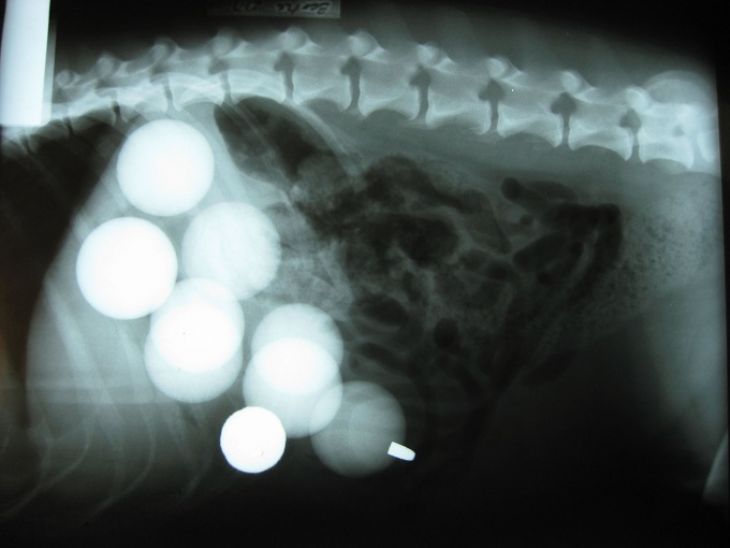

Deväť golfových loptičiek a guľka

Bertieho majitelia prichytili svojho miláčika pri konzumovaní golfových loptičiek. Ihneď s ním utekali na veterinárnu pohotovosť. S prekvapením zistili, že sa mu podarilo prehltnúť až 9 týchto loptičiek a pochutnal si tiež na jednom broku z brokovnice.

(Zdroj: PopSugar)